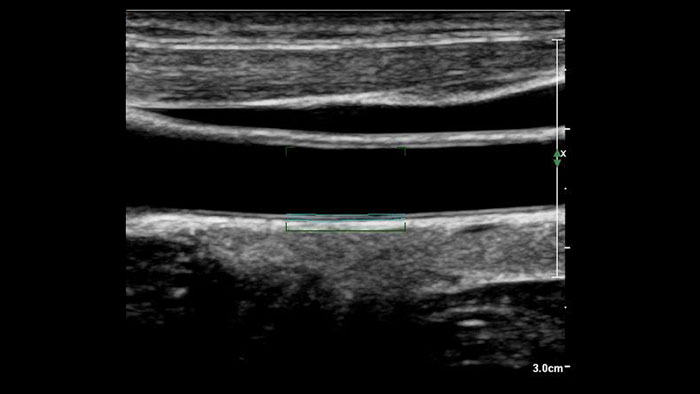

Aplikacja US Q-App Intima Media Thickness (IMT) zapewnia łatwe i spójne pomiary grubości błony wewnętrznej i środkowej tętnic szyjnych i innych naczyń powierzchniowych. Uzyskane wartości IMT można dołączyć do opisu badania pacjenta.

Korzyści